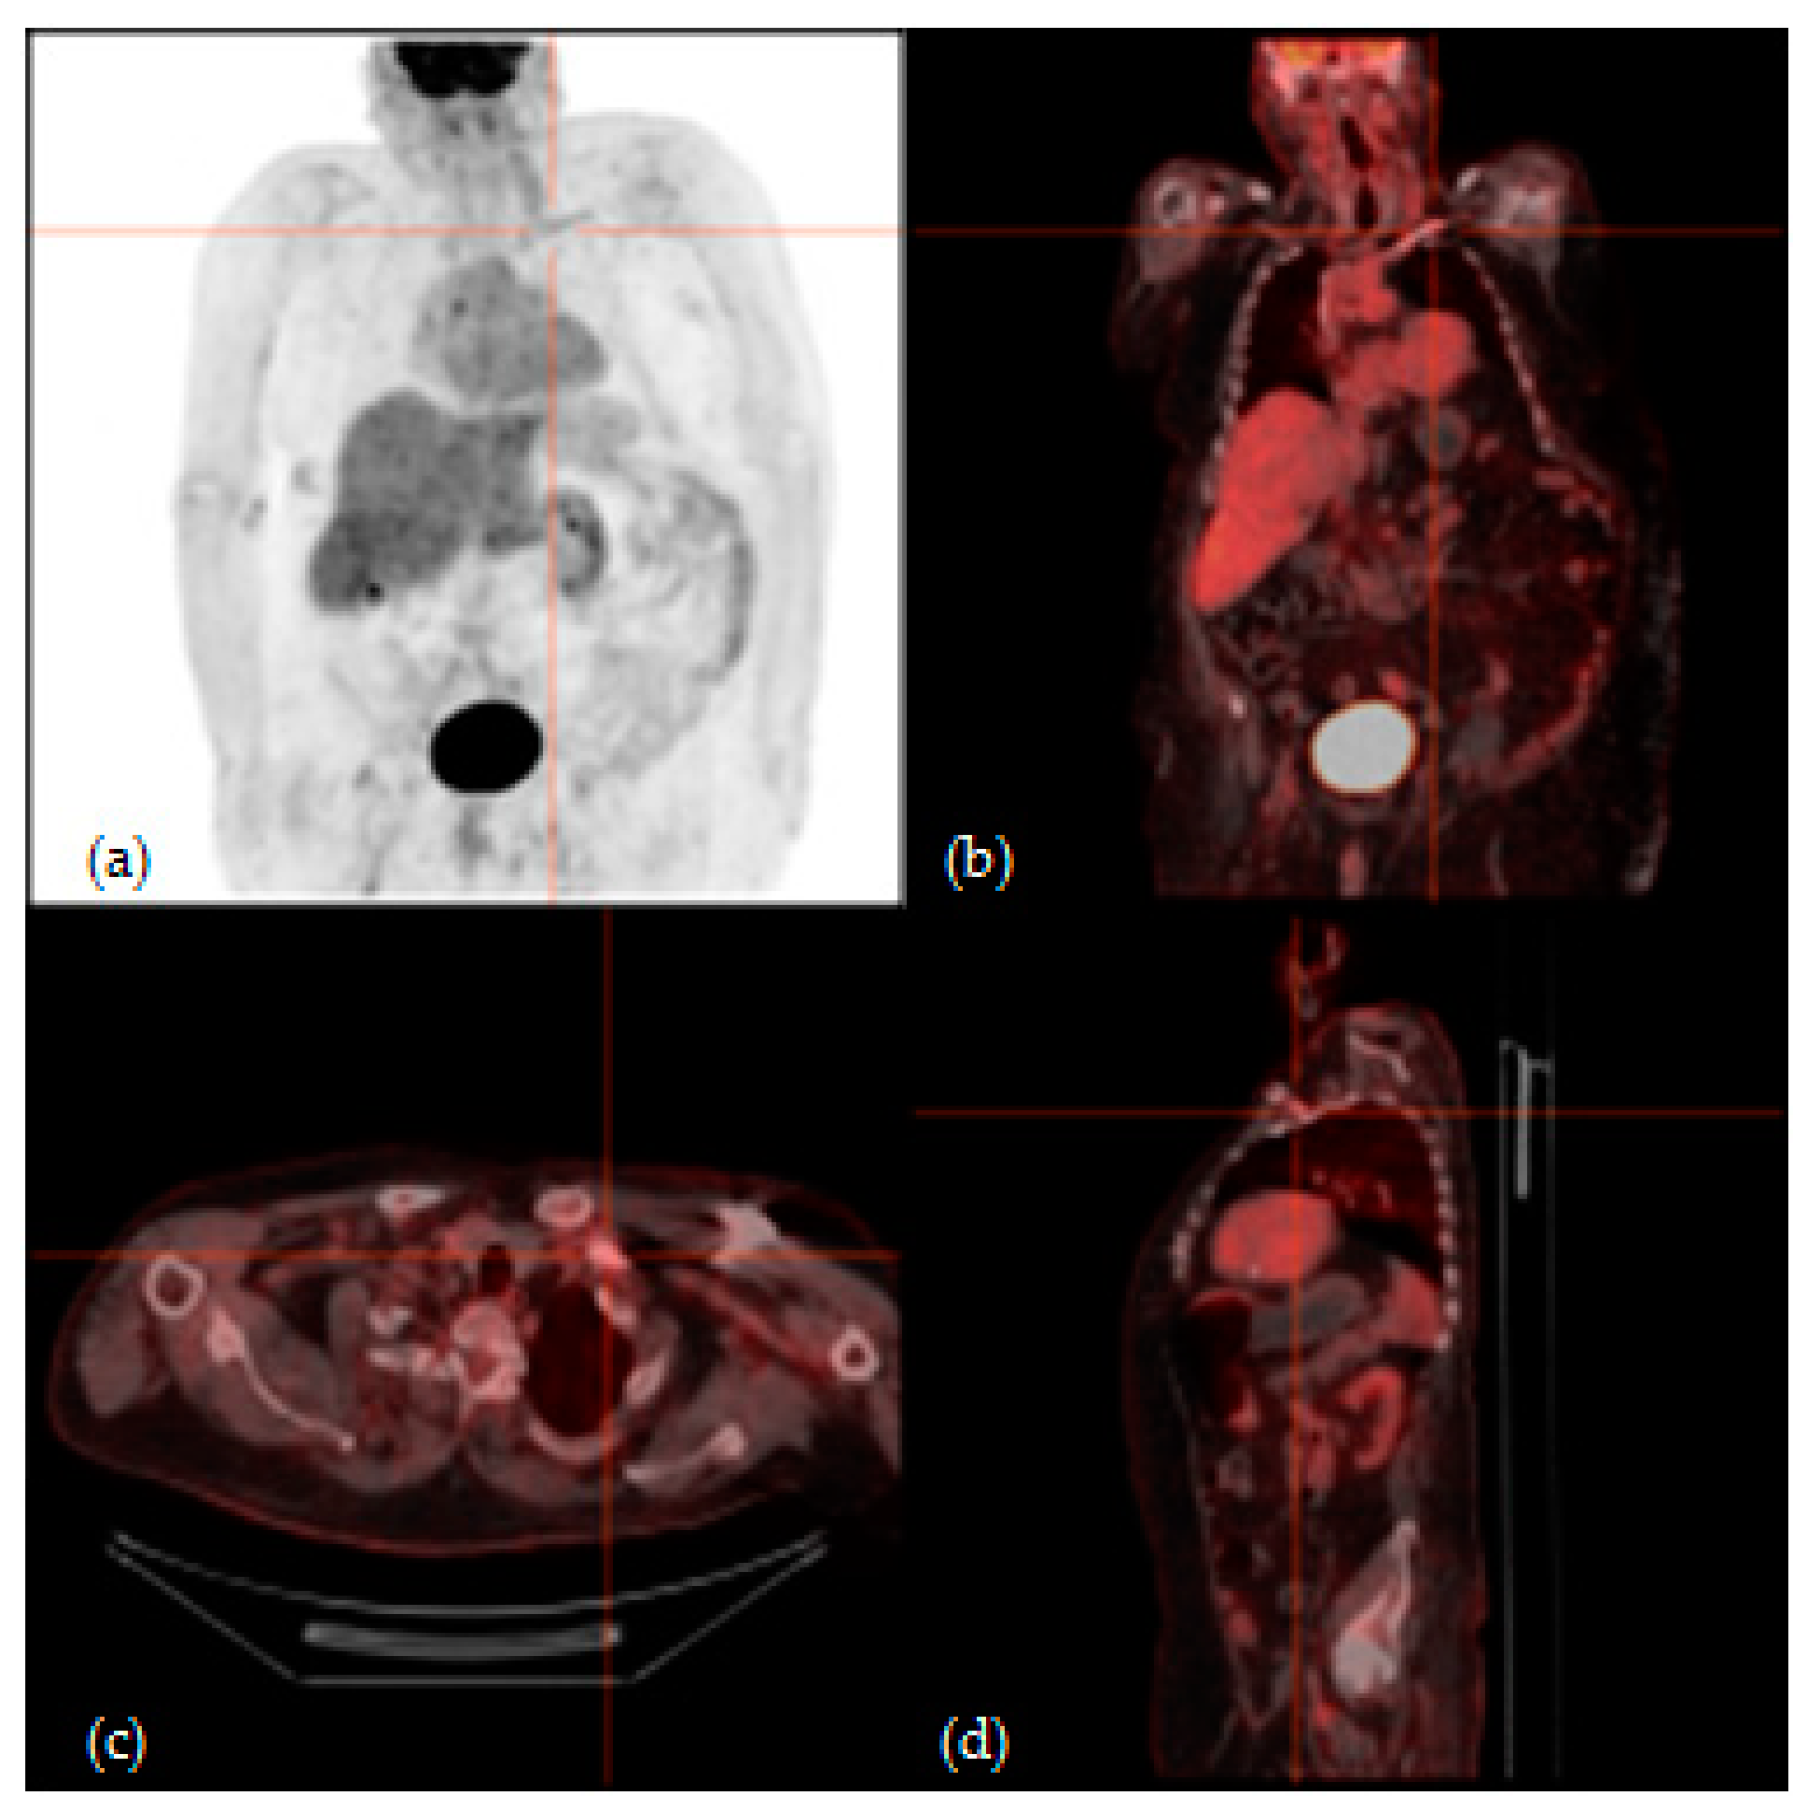

3.2. 18F-FGD PET/CT Analysis Results